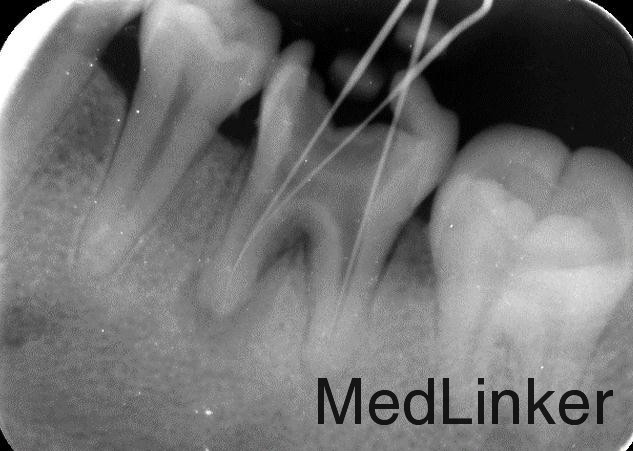

根管治疗加高嵌体修复

效果很好,患者满意